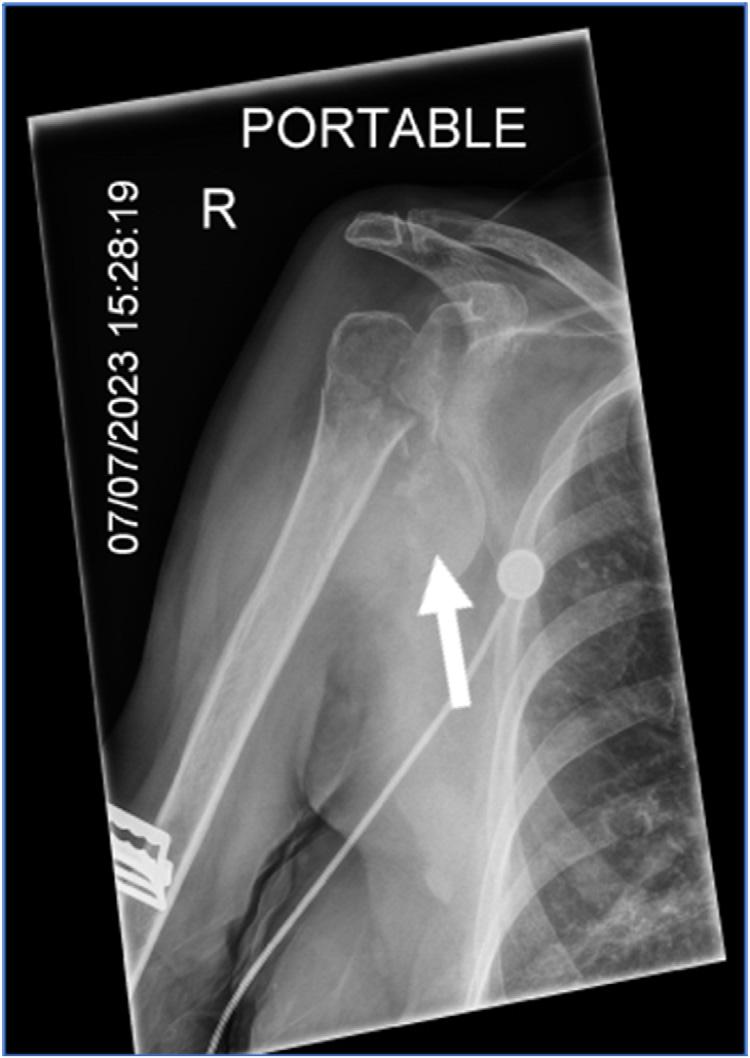

Thepatientwasplacedon100%oxygenvianonrebreathermaskandtransportedtoalocalemergency department(ED).UponarrivalattheEDhedeniednew complaints,andhisvitalsandphysicalexamwerenot significantlychanged.Hiselectrocardiogram(ECG)showed anatrialsensedpacedrhythmconsistentwithpriorECGs. Hehadachestradiograph(CXR)showingleft fifthandsixth ribfractureswithamoderatecircumferentialpneumothorax (Images2 and 3).

Image2. Chestradiographwitharrowspointingtoleft-sidedmoderatecircumferentialpneumothorax.Thereisalossofsymmetry,avisible lungborder,andlossoflungmarkingsuperiortothelungborder.

Image3. Magnifiedviewofthechestradiographdemonstrating fracturesofribs fiveandsix(arrows).